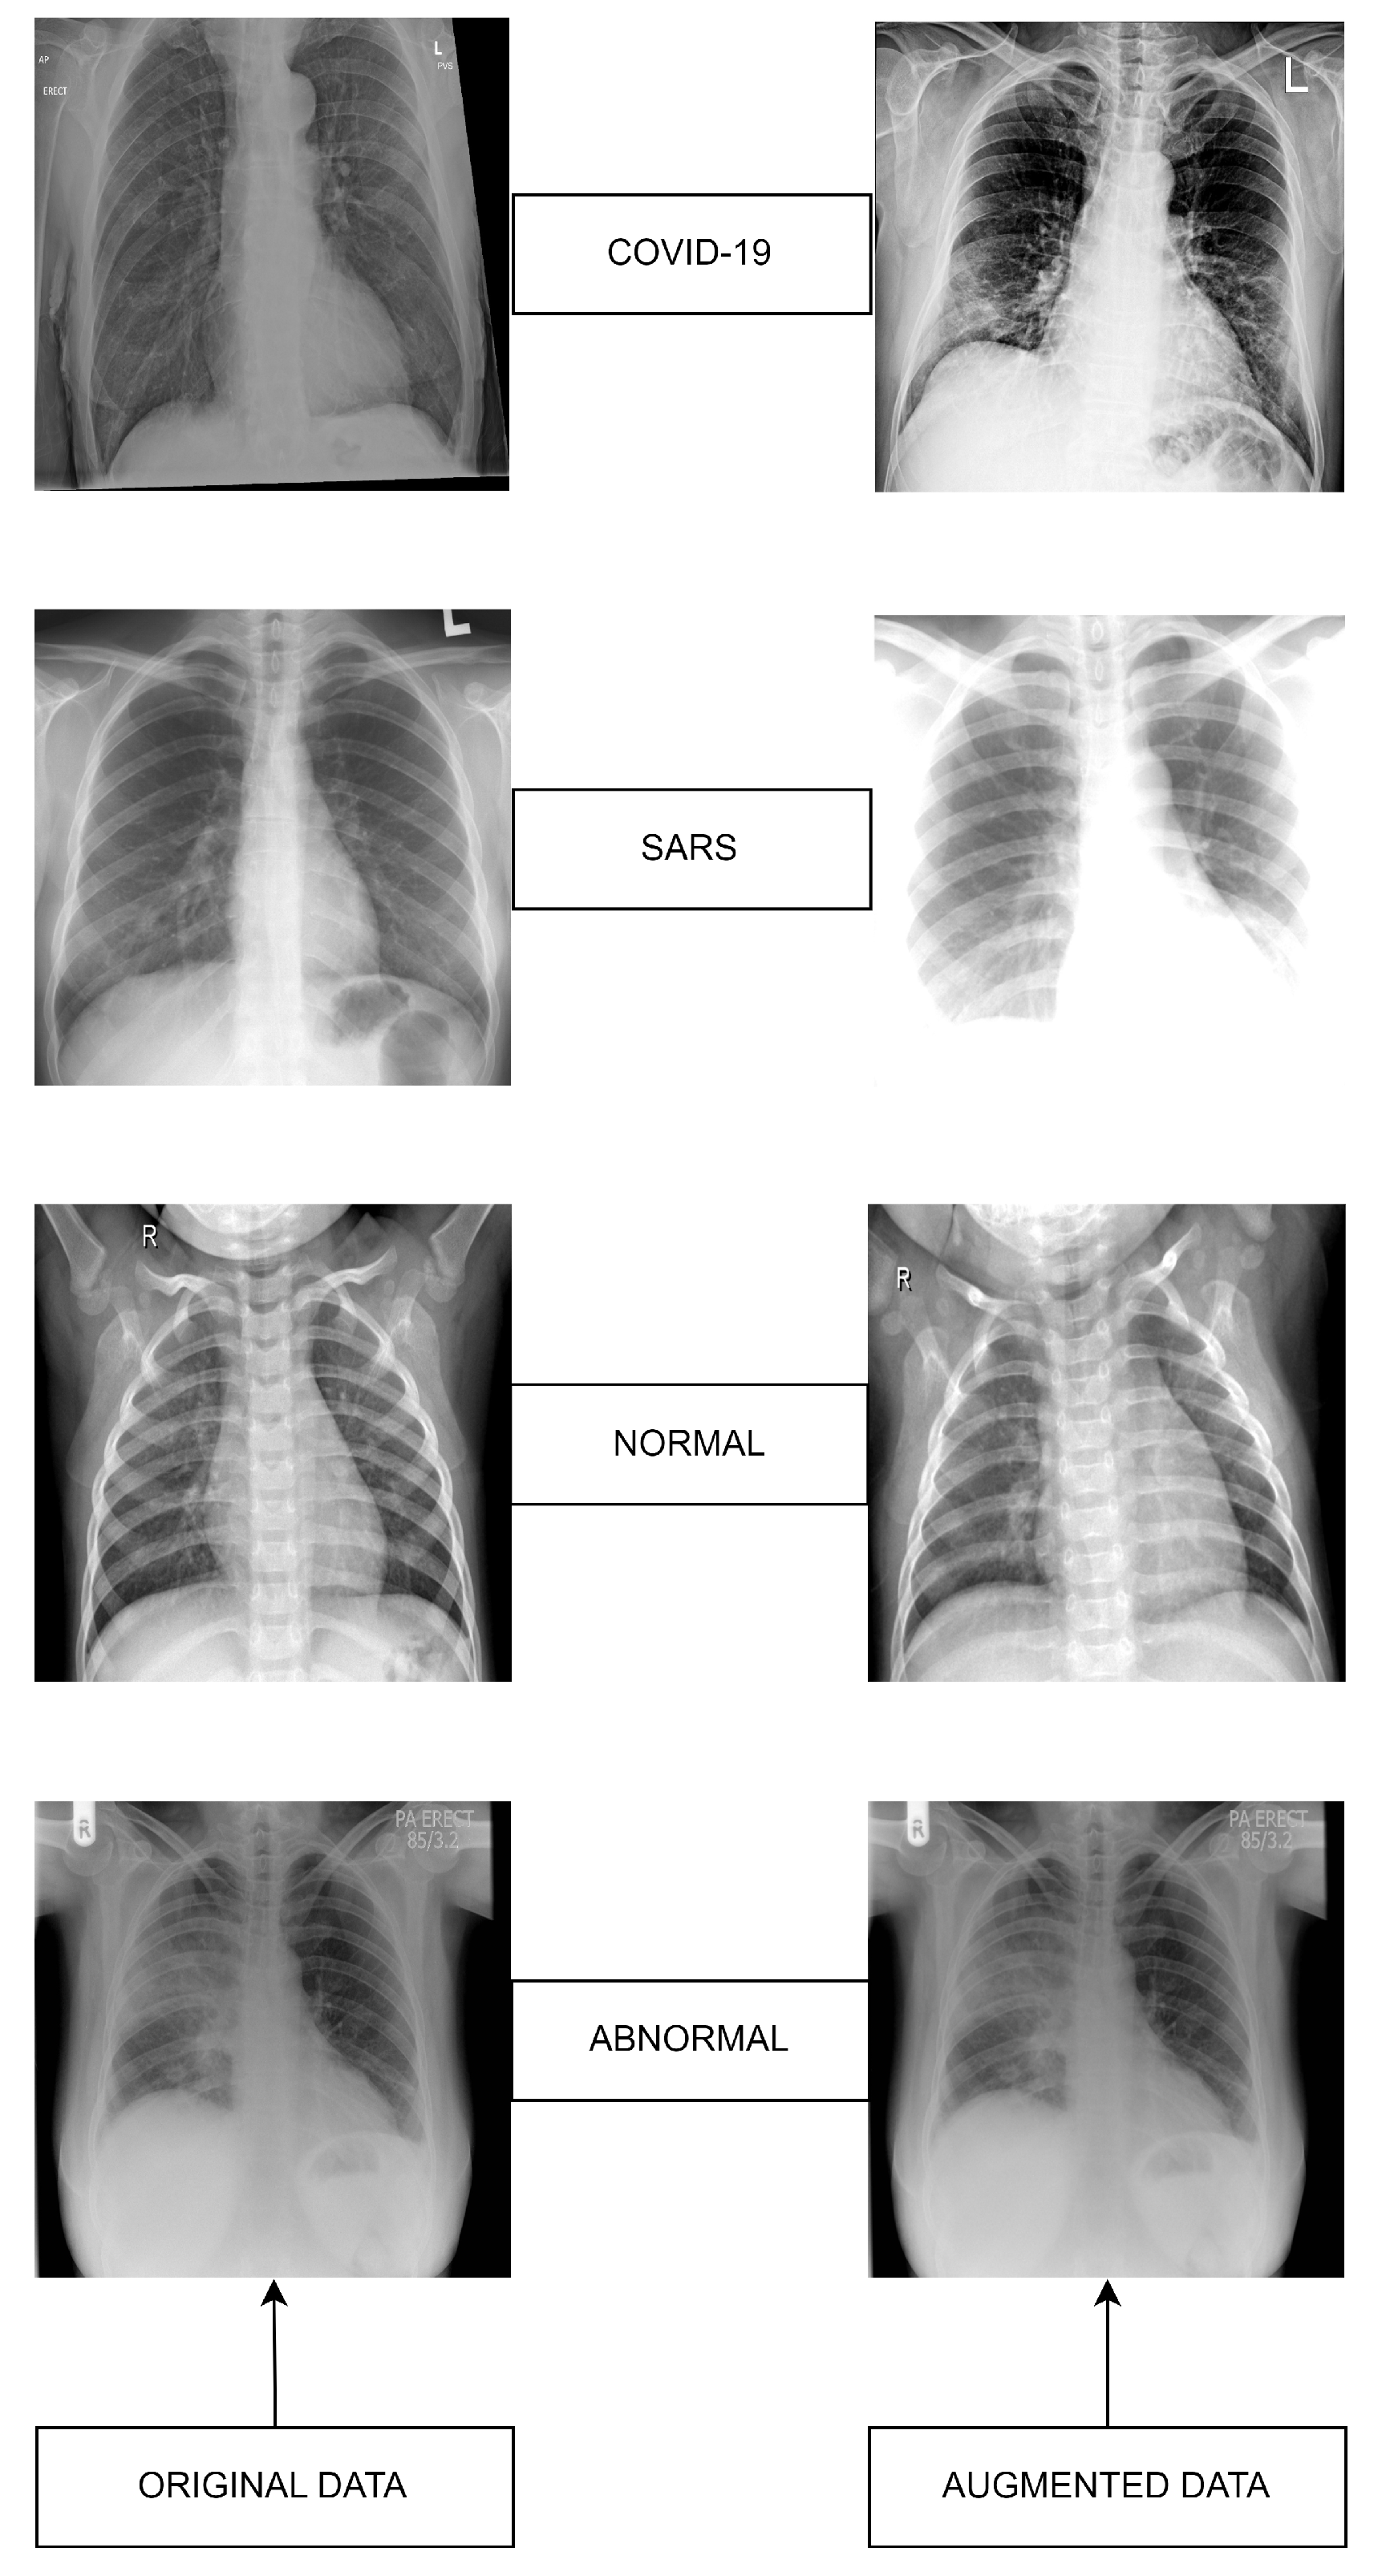

3.1. Datasets

3.2. Original Dataset

3.3. Augmented Dataset